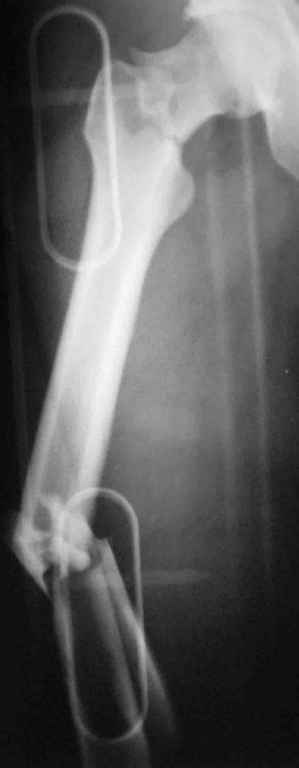

Уважаемый Сергей, избрав вариант DHS плюс ретроградный гвоздь Вы явно обезопасите себя от проблем, связанных с введением штифта через trochanteric fossa. Очень это может быть проблематично, Вы правы. Поэтому DHS плюс ретроградный гвоздь - спокойно выполнимый вариант, особенно в "чужом" отделении. Схожий свой случай из далёкого теперь уже 1999г. прилагаю, только вместо канюлированных винтов у Вас будет DHS (VHS). А если антеградный гвоздь - то только из тех, что предназначены к введению через верхушку вертела. И это тоже выполнимо, но сложнее. Мне так кажется.

Уважаемый Сергей Витальевич! Мы в похожем случае выбрали вариант DHS + DFN. Правда из 4 кортикальных винтов накладки DHS - 2 пришлось вводить монокортикально - уперлись в штифт.. На конечный результат это не повлияло. Ссылка здесь.

К сожалению, послеоперационных снимков в <цифре> нет. Сразу не сделали, а затем <благодарный> больной исчез <из поля зрения>.